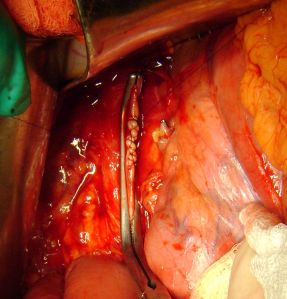

С целью удаления тромба была вскрыта почечная вена у места впадения в нижнюю полую вену, проведено извлечение тромба с последующим ушиванием венозной стенки.

ушивание нижней полой вены